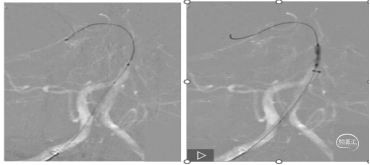

通路建立:8F短鞘,交换8F长鞘、5F多功能导管行脑血管。造影示:左侧颈总动脉闭塞,右侧颈内动脉-前交通动脉向左侧大脑中动脉部分代偿供血;左侧大脑中动脉下干闭塞。

8F长鞘引至左侧颈总动脉,088颅内血栓抽吸导管至颈总动脉-颈内动脉C4段抽吸出大量暗红色血栓。

抽吸后造影示:左侧颈总动脉复通,未见明显血栓逃逸;左侧大脑中动脉下干闭塞同术前。

微导管超选至下干近心端推注5ml替罗非班,后造影示下干部分再通,颈内动脉造影示左侧颈内动脉-大脑中动脉复通,eTICI 3级。